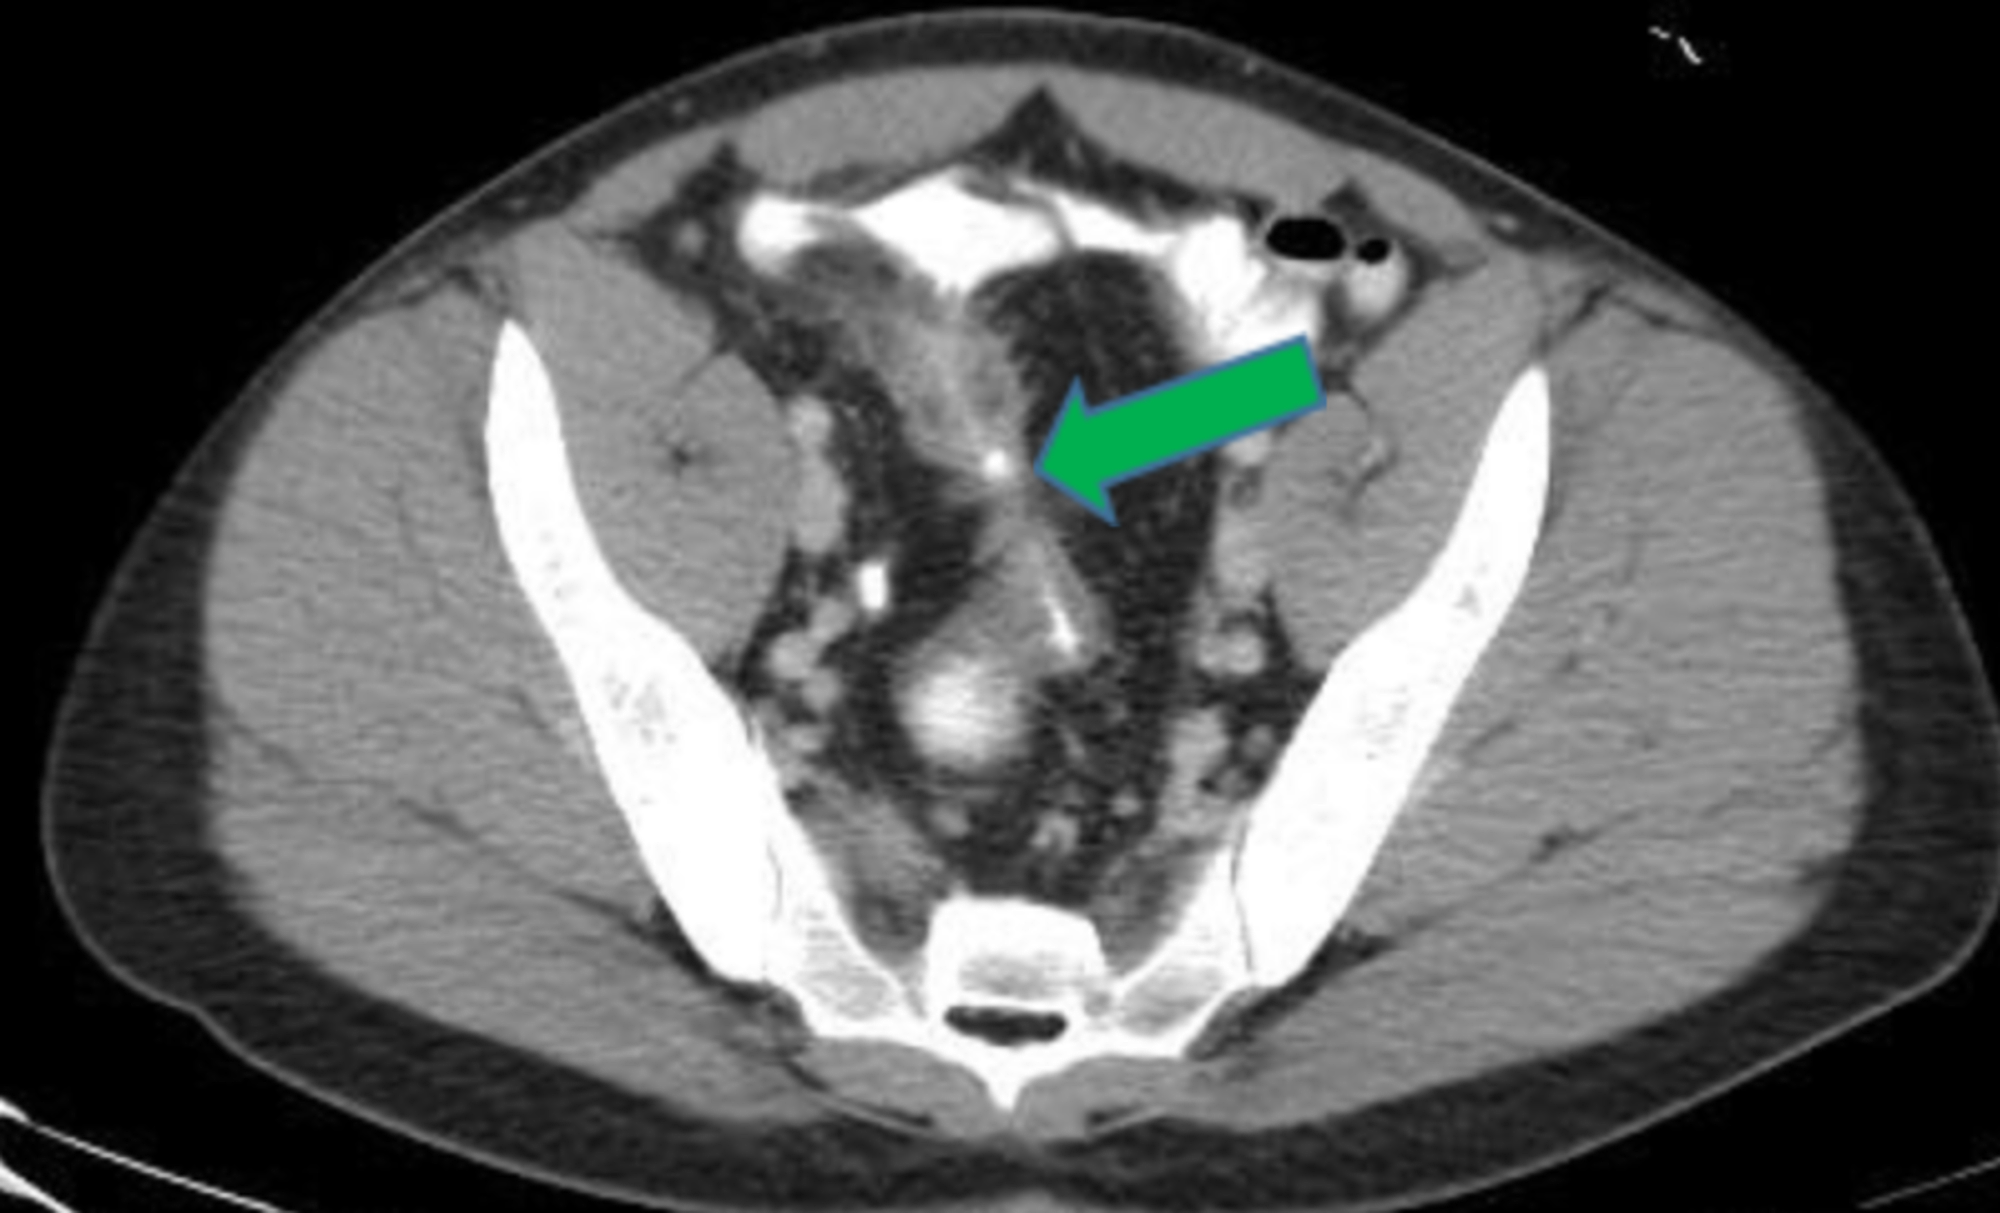

Urinary complications in Crohn’s disease and ulcerative colitis

(PDF) Crohn’s Disease and Urinary Manifestations A Crohn’s Intestinal Crohn's Disease Urine People diagnosed with crohn’s disease have a higher risk of developing kidney stones in the urinary tract than those without crohn’s, including those with ulcerative colitis. In people with crohn’s disease, hydronephrosis often occurs in the right kidney, close to the terminal ileum. Cystitis was the most common. Increased urination is one possible symptom of. Inflammatory bowel disease (ibd) is. Crohn's Disease Urine.

Crohn's disease. Contrastenhanced CT scan shows distal ileal loops Crohn's Disease Urine Ulcerative colitis (uc) and crohn disease (cd). People with ulcerative colitis are more likely to develop kidney stones — hard deposits of salts and minerals in the kidneys. Increased urination is one possible symptom of. Inflammatory bowel disease (ibd) is comprised of two major disorders: Cystitis was the most common. Crohn’s disease is a lifelong condition that causes inflammation in. Crohn's Disease Urine.